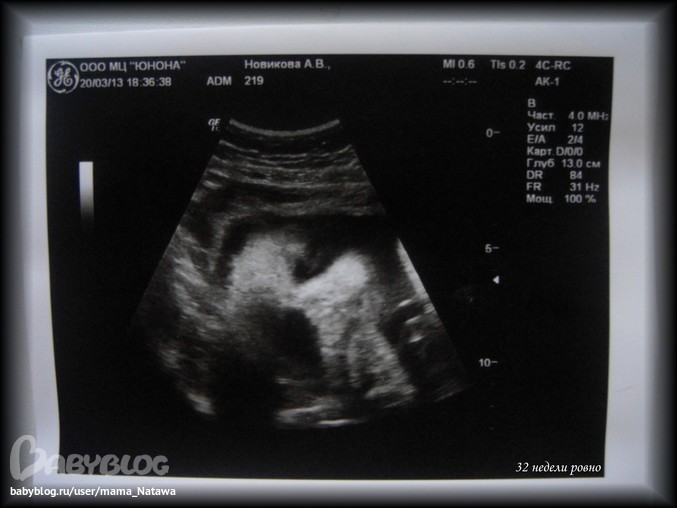

Теперь про УЗИ:

Ходили мы как всегда с папой ))) сначала малыш спал - мы его разбудили

Ах, да ))))))))))))) мальчик мой перевернулся с попки головой вниз!!!

так что мы теперь правильно лежим )))

- 1 живой плод в головном предлежании

- Бипариетальный размер головы = 8,09 см

- Окружность головы = 29,18 см

- Диаметр/окружность живота = 25,36 см

- Вес = 1 617 гр.

сказала, что нормальный (не крупный и не маленький)

- Плацента по передней стенке матки, больше справа в дне. Степень зрелости = 1, что соответствует сроку беременности

- Количество вод = нормальное

- Врожденных пороков не обнаружено

- Беременность 31 неделя 4 дня (хотя ББ ставил 32 недели ровно...) дату родов сдвинула на 18.05, но сказала ориентироваться на 15 ))) как мы и делаем!

Всё у нас по параметрам хорошо

ТТТ ))))))) всё соответствует сроку!